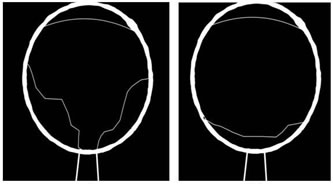

INTRODUCTION The retina, as we know, is a layer of organized neurons which line the posterior portion of the posterior chamber of the eye. The retina consisting of photoreceptors, neurons and support cells, is lined anteriorly by the vitreous and posteriorly by the choroid, and has a central portion called the macula. The macula has a high concentration of photoreceptors and is responsible for capturing central vision. More precisely there is a 1.5 mm central portion in it with the highest concentration of photoreceptors called the fovea, which forms the basis of classification of Mac- On and Mac- Off retinal detachment. Normal anatomical landmarks of the eye as visualized on ultrasonographic imaging are depicted in Figure 1. Figure 1: Normal anatomical landmarks of the eye on ultrasonographic imaging RD (Retinal Detachment) occurs when this layer separates from the underlying epithelium, resulting in ischemia and leading to progressive photoreceptor degeneration which might result in complete blindness of the affected eye if not properly treated or even with delayed treatment and surgeries performed beyond the stipulated time period1, 2 Depending on the type of retinal detachment, the time interval of the surgical treatment is the key to preservation of vision.3 Retinal detachments as described are of three types4: Rhegmatogenous RD (RRD), Tractional RD (TRD) and Exudative and Serous RD. RRD is the most common, and is caused by a tear in the retina (‘Rhegma’ meaning ‘tear’) with consequent extension of vitreous into the potential space below the retina and separation of retina from choroid, requiring surgery. TRD is caused due to pre-retinal membrane formation and scarring which pulls away the retina from its attachment. It is seen in diabetes, trauma, Eales disease and sickle cell retinopathy also indicating surgery. Exudative and Serous RD is less common and along with TRD will not be referred in this study. Rhegmatogenous Retinal Detachment (RRD) can be of two types: Mac- Off and Mac- On RRD. Mac- Off (Macular- Off) rhegmatogenous retinal detachments occur when the retinal detachment also involves the macula and extends to the fovea. Mac- On (Macular- On) retinal detachments on the other hand spare the macula and do not extend to the fovea.4 (Figure 2) a b Figure 2: Ultra-sonographic images of a) Mac- On and b) Mac- Off Retinal Detachments Ultrasound has been evolving in the background of vast advancements in MRI and CT scans in the field of Radiodiagnosis and has proved to be an effective, safe and cost effective radiological investigation giving enormous information in minimum time. However radiologists mostly tend to limit themselves to abdominal or fet al. ultrasound leaving small part ultrasounds mostly to the experts. An area not so commonly explored is ultrasounds or B scans of the eye. It has been found that visualization of the eye is equally possible with a routine ultrasound machine even without the availability of a B scan. Orbital ultrasounds are regularly referred to the Department of Radiology for various pathologies including screening to rule out retinal detachment, particularly prior to cataract surgeries or following trauma or infections of the eye. Radiologists predominantly suffice themselves by reporting the absence or presence of retinal detachment. No classification of the type of retinal detachment is investigated beyond this finding, in majority of the cases. Mac- Off and Mac- On, as described above are classifications of retinal detachment which are less known and very rarely reported by the radiologists, and yet are findings which hold urgent importance in the final outcome of the patients’ vision being restored. Differentiating these two types of retinal detachment give crucial evidence for the outcome of the treatment planned by the ophthalmologist besides giving critical time frame for performing any surgery planned on the affected eye. Overlooking this simple data and a lack of reporting and understanding of the value of this finding may lead to an erroneous miscalculation of the time of surgery and a delay in the surgery, based on this data provided by the radiologist, leading to total permanent blindness. Not only does this radiological finding gives crucial data allowing prompt surgery and saving of the vision, but also provides any unnecessary medico legal repercussions. Retinal detachment on ultrasounds appears as an echogenic linear floating membrane which is attached to the optic disc, differentiating it from PVD (posterior vitreous detachment) where the optic disc is free of the attachment of the membrane.4, 5 (Figure 3) Mac- Off RD can be visualized on ultrasounds as retinal detachment with retina lifted away from the fovea, whereas in Mac- On RD, the retina is attached at the fovea sparing the macula. Mac– Off and Mac– On classification of RD are relatively less known entities and rarely reported or evaluated. Findings of Mac- On RD on urgent sonographic evaluation become critical, requiring urgent surgical repair to prevent total blindness.

Figure 4: Mac- Off retinal detachment with V shaped configuration. An attachment of the detached membrane eccentrically and temporally at the fovea indicated Mac- On RD, indicating preservation of the macula. On the other hand no attachment of the membrane at the fovea, but only attachment centrally at the optic disc indicated a Mac- Off RD, with no preservation of the macula. In both cases the results were immediately conveyed to the concerned ophthalmologists for immediate follow up. It was conveyed that cases of Mac- On RD were to be immediately treated within 24 hours to preserve the central vision. And in cases of Mac-off RD a period within 7 to 10 days were indicated for treatment and surgery. All 9 cases of Mac- On RD were immediately referred for corrective surgeries and showed preservation of eyesight in affected eyes subsequently. The results stressed the need for immediate and correct diagnosis by the radiologist performing the ultrasound of the eye, followed by prompt surgeries within 24 hours. In regards to the time period since first clinical symptoms of the affected eyes, it was found that all 9 cases of Mac-On RD, had reported within a few hours of their eye being affected and immediately contacted the ophthalmologist. On the other hand patients, who had been diagnosed with Mac- Off RD, had contacted 2 to 10 days after the eye had been clinically affected.

DISCUSSION The field of Radiology has encountered tremendous technological advancement since the past few decades and is still progressing and evolving. It is up to the modern radiologists to further the knowledge acquired by their peers. One such area which is less explored and requires attention is in cases of ultrasounds of the eye or B scans. Even without a dedicated B scan, excellent ultrasounds are possible with routine ultrasound machines. Moreover, ultrasounds that are generally performed by the radiologists are simply reported to identify and diagnose retinal detachment, with no further differentiation between Mac- Off and Mac- On RD thereby excluding critical data from contacting the ophthalmologist. Such incomplete ultrasound reports might be detrimental in the final outcome of the preservation of vision in the affected eye of patients with retinal detachments.3 Accurate sonography assessment and understanding of retinal detachment and its variations is crucial in the ultimate efforts to maintain vision in the affected eye.2, 6 In the preliminary ultrasound assessment it is necessary to establish the efficacy of the vitreous chamber and whether there are any echogenic areas or membranes within it. In the presence of membranes, the next step would be to establish retinal detachment.4 The primary differentiation is from PVD (Primary Vitreous Detachment). Posterior attachment centrally or eccentrically, reduced after movement on dynamic ocular ultrasound and visualization of membranes on normal gain settings of ultrasound confirm diagnosis of retinal detachment. On the other hand PVD is without any posterior attachment, significant after movements on dynamic ocular ultrasound with visualization mostly on high gain settings on ultrasound. Once ultrasound establishes existence of retinal detachment, the next step is to differentiate Mac-On RD from Mac- Off RD.7 Mac- On RD would be sparing the macula and in this case the membrane of detached retina is attached eccentrically at the fovea [5] advocating prompt surgical intervention within 24 hours to preserve central vision.1, 2, 8 In Mac- Off RD, macula is not spared, there is no preservation of central vision and the detached retinal membrane displays the characteristic central attachment at the optic disc and V shaped configuration. This is more commonly seen possibly due to a delay in the time of performing the ultrasound and progression of Mac- On RD to Mac- Off RD. The Mac-off RD is retinal detachment where central vision has already been compromised due to involvement of the macula and hence does not warrant immediate surgery, and could be performed within 7 – 10 days. In the current study, 9 cases of Mac-On RD, had reported within a few hours of their eye being affected and had contacted the ophthalmologist who had immediately recommended an ultrasound of the eye. This promptness by the patient and treating doctors were key factors in success of the treatment. On the other hand patients with Mac- Off RD had appeared 2 to 10 days after the eye had been clinically affected possibly indicating a progression of an initial (undiagnosed ) Mac- On RD progressing to Mac- Off RD due to lack of medical attention in the appropriate time frame. Hence it is important for the patient, ophthalmologist and particularly the radiologist to understand that prompt and early consultation and correct data acquisition and reporting by the radiologist is essential in such cases to preserve vision in cases of retinal detachment. It is to be stressed that simply diagnosing RD from other pathologies, particularly PVD is not enough. Further differentiation of RD into Mac- Off and Mac- On RD needs to be an essential modality in reporting of RD. Early identification and knowledge of the differentiation of the two types of retinal detachment could initiate the patients and doctors to go in for an early ultrasound within the first few hours of the eye being affected, to allow the surgeon to intervene and preserve crucial vision.3